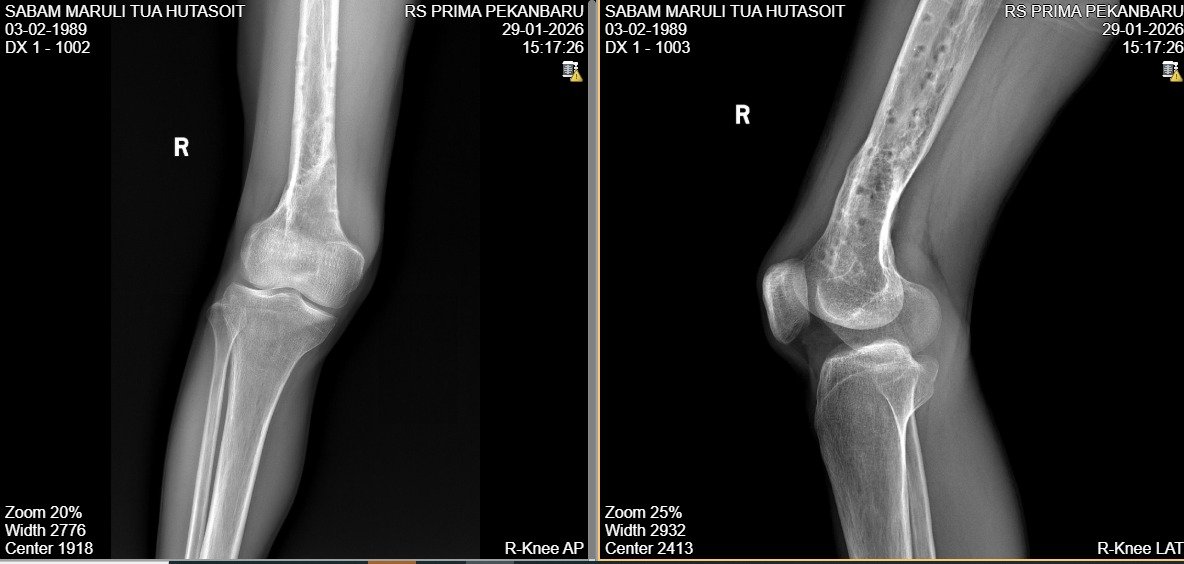

Sabam diketahui masih menjalani pemeriksaan dan pengobatan di bawah penanganan dr. Mardiansyah di Prima Pekanbaru. Surat keterangan medis tertanggal 5 Februari 2026 secara tegas menyatakan yang bersangkutan masih harus beristirahat dan belum layak kembali bekerja. Namun, PHK disebut telah dilakukan lebih dahulu pada 25 November 2025.

Fakta bahwa pada 5 Februari 2026 dokter masih menyatakan Sabam belum pulih, memunculkan pertanyaan serius mengenai keabsahan dan prosedur PHK yang dilakukan sebelumnya.